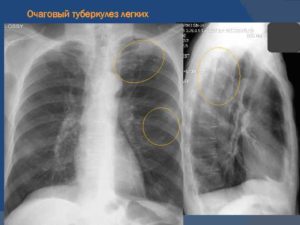

Очаговый туберкулез легких: заразен или нет, лечение в фазе инфильтрации, двухсторонний рентген, симптомы распада верхней доли правого легкого

Очаговый туберкулез легких — это вид вторичного заболевания, которое протекает с образованием в органах дыхания воспалительных очагов. В большинстве случаев болезнь практически не имеет выраженных симптомов, поэтому нередко ее выявляют при флюорографическом обследовании.

Рентгенологические признаки

Пациенту проводят рентген легких в 2 проекциях. При свежем заболевании на снимке очаги представлены в виде теневых образований небольшого и крупного размера, имеющих округлую форму.

Нередко они локализуются в верхних отделах легких. Для хронической формы патологии характерны плотные фокусы с очагами фиброзных тяжей.

При фиброзе ткани легкого мелкие очаги соединяются и перемещаются к верхушке легкого, а к плевре тянутся тени в виде полос.